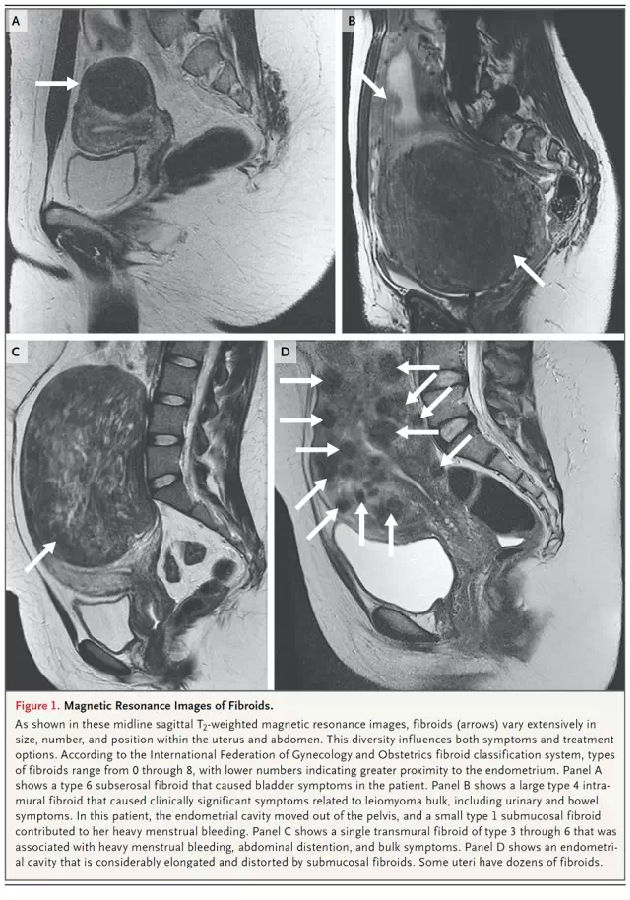

诊断:FIGO有关肌瘤的分型参见下图。超声是诊断首选。增强MRI可以为变性肌瘤提供更多的信息,可以更好地区别肌瘤和内膜、浆膜之间的关系。是否以超声年度监测肌瘤进展,仍无明确证据。一项MRI每半年的检查发现,肌瘤变化从缩小89%到长大138%,中位是增大9%。很多肌瘤会突然增大。指南认为,肌瘤突然增大并不是治疗的指证。出血过多的女性应该评估出血的严重程度和后果,检查血常规和甲状腺功能。选择性的筛查方案包括对认知功能的检查(尤其是von Willebrand’s病,或有相关个人史、家族史)、内膜活检(有内膜癌高危因素的女性,如肥胖,慢性无排卵,应用雌激素治疗但没有孕激素拮抗)。微创术中肌瘤粉碎术所发现的恶变率为1/300,这个数字在小于40岁的女性中其风险为1/1500,40-44岁间为1/1100。类似肌瘤的恶性病变(平滑肌瘤,癌症)的高危因素包括:盆腔放疗史,应用他莫西芬,罕见的遗传综合征等。

治疗:症状本身提供治疗选择的信息。没有证据支持常规治疗无症状的子宫肌瘤。图1是不同症状表现患者的MRI表现。